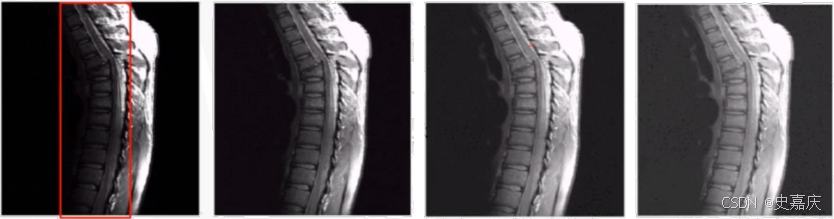

如下图,是人体上部脊椎骨折核磁共振图像,左边第一幅图为原始图片,暗部比较重。其余3张图片不同程度增强了暗部层次。从左往右依次 γ = 0.6 , 0.4 , 0.3 \gamma=0.6,0.4,0.3 γ=0.6,0.4,0.3